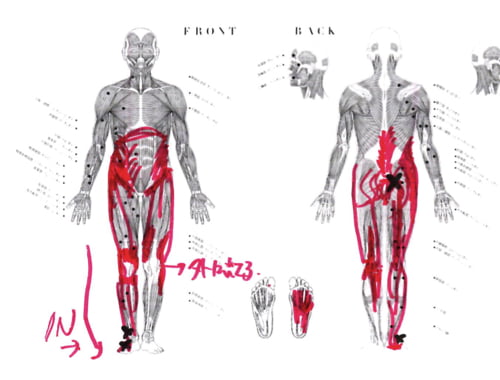

実際にお身体の状態を診せて頂くとこんな感じでした。

Xは痛みの場所。赤い線は筋肉や腱の硬直やヨジレ。

腰や足首の痛みの場所も氣になりましたが

僕はこの膝のヨジレや曲がりもとっても氣になりました。

この膝のヨジレは腰や足首への影響も大きいと考えています。

施術はまず足首から足の甲、そして膝へ繋がるこれらの筋肉や腱を調え直しました。

図で分かるように足の甲から膝へ、足裏から膝へと繋がっています。

そして膝から上は腰骨に繋がっているので、膝は足首にも腰にも影響があるのです。

足の裏はかなりヨジレもあり張っていました。

ズバリ足首の痛みの原因はこの足裏のヨジレ。

そして足裏の不調が膝を歪め、腰に痛みを生み出しています。

膝下から足先までの施術が終わった状態はこんな感じです。

施術前の膝のヨジレや曲がりが少し穏やかになっています^^

この段階で足首から足の甲の痛みは消えています。